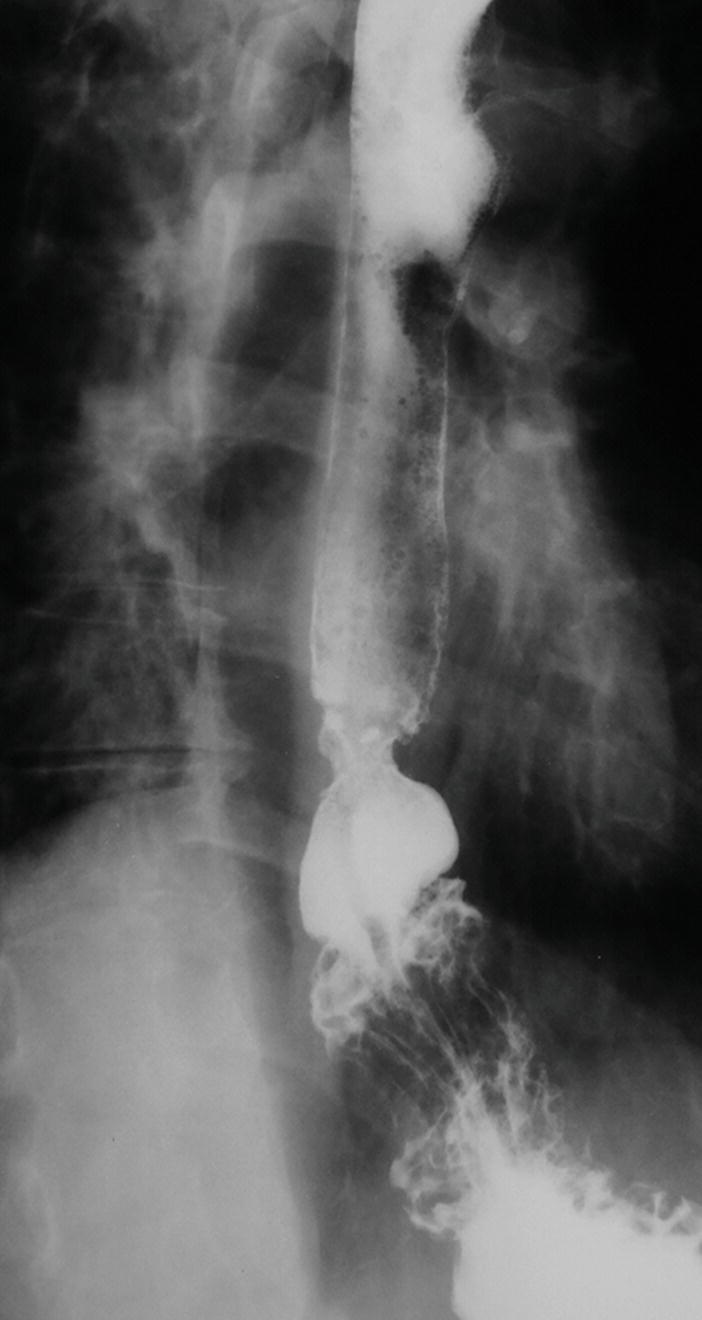

from radiologykey.com

Pharynx and Esophagus Radiology Key

Pharynx and Esophagus Radiology Key Peristaltic Stripping Wave Achalasia is the esophageal motility disorder of. nutcracker esophagus, which also classically presents with chest pain and dysphagia, is characterized manometrically by a mean distal esophageal. we hypothesize that patients who are categorized as having weak or frequent failed peristalsis and undergo standard. as the inhibition ends, sequential activation of excitatory (cholinergic) neurons in the rostral dmn. Peristaltic Stripping Wave.